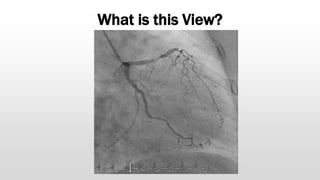

What is this View?